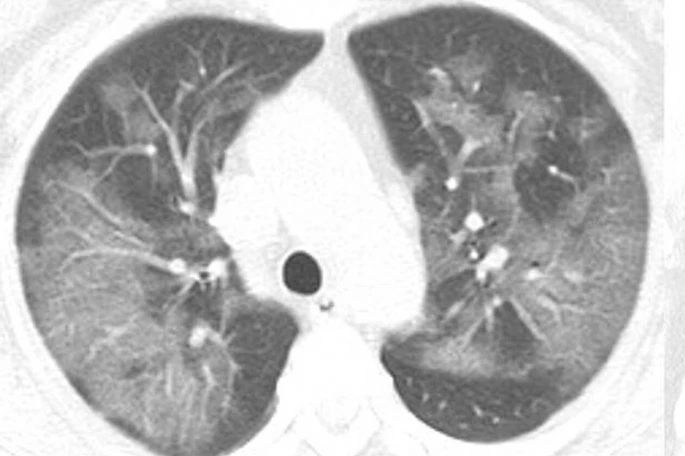

Η πανδημία του κορωνοϊού covid-19 συνεχίζει να καλπάζει σε όλο τον πλανήτη, με τους γιατρούς να παρακολουθούν την έξαρσή του. Περισσότεροι από 4.000 άνθρωποι έχουν χάσει τις ζωές τους από τις επιπλοκές του ιού, ο οποίος προκαλεί σοβαρό πρόβλημα στους πνεύμονες των ασθενών. Στην δημοσιότητα δόθηκαν από την Ραδιολογική Κοινότητα της Βορείου Αμερικής ακτινογραφία πνευμόνων ασθενών, οι οποίοι είχαν προσβληθεί από τον κορωνοϊό, οι οποίες προκαλούν ανατριχίλα.

Οι ασθενείς που έχουν νοσήσει μέχρι στιγμής έχουν περιγράψει την εμπειρία τους ως μια «τρομακτική προσπάθεια για να αναπνεύσουν». Στις ακτινογραφίες διακρίνονται κάποια άσπρα σημάδια, χαμηλά στους πνεύμονες. Περιγράφονται ως υγρό στις κυψέλες του πνεύμονα. Να σημειώσουμε πως οι ακτινογραφίες αυτές που δόθηκαν στην δημοσιότητα είναι από ασθενείς από την Κίνα που νόσησαν με επιπλοκές, οπότε δεν έχουν καμία σχέση με το αν νοσήσει κάποιος ο οποίος δεν αντιμετωπίζει προβλήματα υγείας.